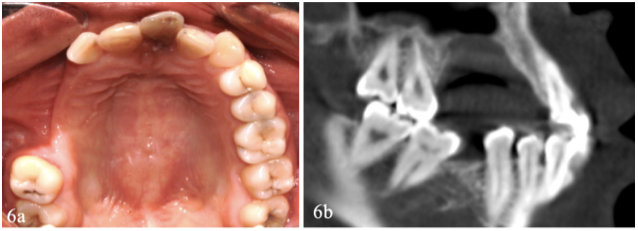

En el examen histológico de cortes representativos del tumor identificaron las características del cementoblastoma. La figura 5 (a) muestra la cápsula de tejido fibroso que envuelve al tumor, el cual se continúa con el estroma presente entre las trabéculas de cemento desorganizado. La figura 5 (b) muestra la zona de reabsorción por reemplazo o sustitución a nivel de la dentina radicular, se ve que el tumor ha perforado el cemento normal del diente y se fusiona con la dentina reabsorbida, La figura 5 (c y d) muestra trabéculas gruesas de contornos irregulares formadas por cemento desorganizado con un estroma de tejido conectivo laxo vascularizado que contiene cementoblastos voluminosos adosados a las trabéculas de cemento y algunos cementoclastos. No se distinguían mitosis. El control clínico y radiográfico a los 8 meses no evidenciaba recurrencia del tumor (figura 6 (a y b)).

El cementoblastoma es una neoplasia que tiene un crecimiento continuo que puede producir perforación de las corticales, su recurrencia ha sido estimada en 37,5% en un seguimiento de 5 años y en 11,8% en control de 2 años y medio respectivamente (12,13), la recurrencia ocurre cuando queda parte del tumor después de un tratamiento quirúrgico incorrecto. En el caso presentado el tratamiento fue remoción en bloque que incluyó, además del tumor y la premolar, a las piezas 13 y 16 que estaban contiguas. El control a los 8 meses confirmó que el tratamiento fue correcto (figura 3 (a y b)), La ausencia de dientes y el defecto óseo alveolar resultados del tratamiento quirúrgico serán solucionados mediante una prótesis parcial removible.